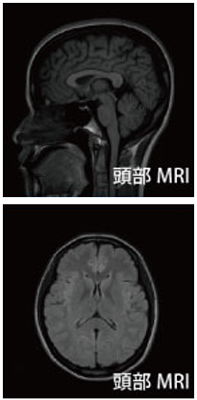

検査の最も中心となるのがMRI装置を用いた画像診断です。頭部の内部を磁気を用いて輪切りにして観察します。脳梗塞、脳出血、まだ症状の出ていない無症候性脳梗塞、脳腫瘍、脳萎縮などが分かります。また同じMRI装置を使って、脳の血管、頚部の血管を見ることができます。これをMRA(血管撮影)といいます。これにより脳動脈瘤の有無や、脳の血管の細くなっているところを立体的に見ることができます。